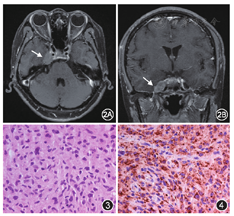

肿瘤是本组海绵窦区病变第二位病因,其中以脑膜瘤最常见。本组患者三叉神经第二支受累多见,与其他组比较差异有统计学意义(χ2=5.213,P=0.022,表3)。本组肿瘤患者中,有4例(9.3%)早期诊断为THS接受激素或其他免疫治疗,随访时确诊为肿瘤性疾病,包括淋巴瘤1例,腺性囊样癌1例,乳腺癌转移1例,肺癌转移1例。本组1例海绵窦原发性组织细胞肉瘤,为国内首例报道。患者女性,51岁,亚急性起病,头痛复视1个月,MRI示右海绵窦病变(图2),曾在外院诊为THS而接受激素治疗。手术病理证实为组织细胞肉瘤(图3,图4),术后半年死亡。